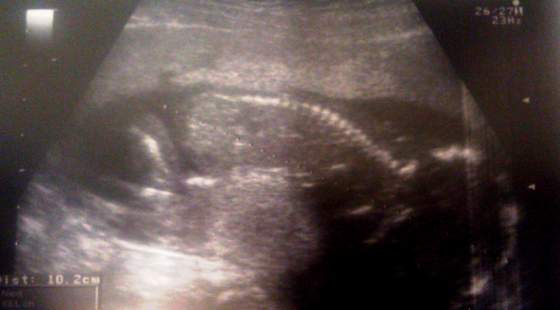

dzidzia zdrowa, ma już 10,2cm i waży 180g

Gin zrobiła bardzo dokładne USG, najpierw zaczęła dowcipnie,potem przeszła na brzuszne, pomierzyła wszystkie kości,obwody itp

Serce bije, jest prawidłowe 4komorowe, widać już żołądek i nerki, mózg prawidłowy, bez przepuklin itp itd.... Powiedziała że za 4tyg pomierzymy wszystko i posprawdzamy bardzo dokładnie, ale że już dziś bardzo dużo udało jej się zobaczyć i wszystko jest ok, więc ona jest spokojna i dobrej myśli

a co najważniejsze? BĘDZIE DZIEWCZYNKA!!!!

A tu foty: